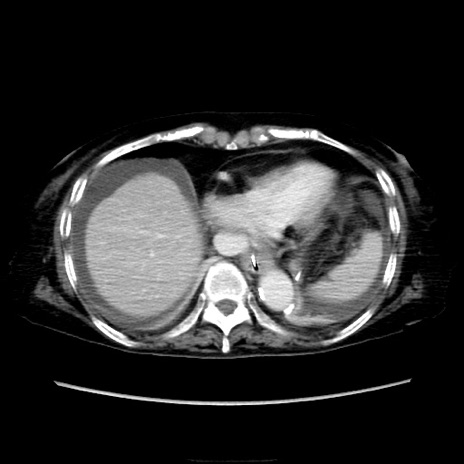

他院CT

横断像